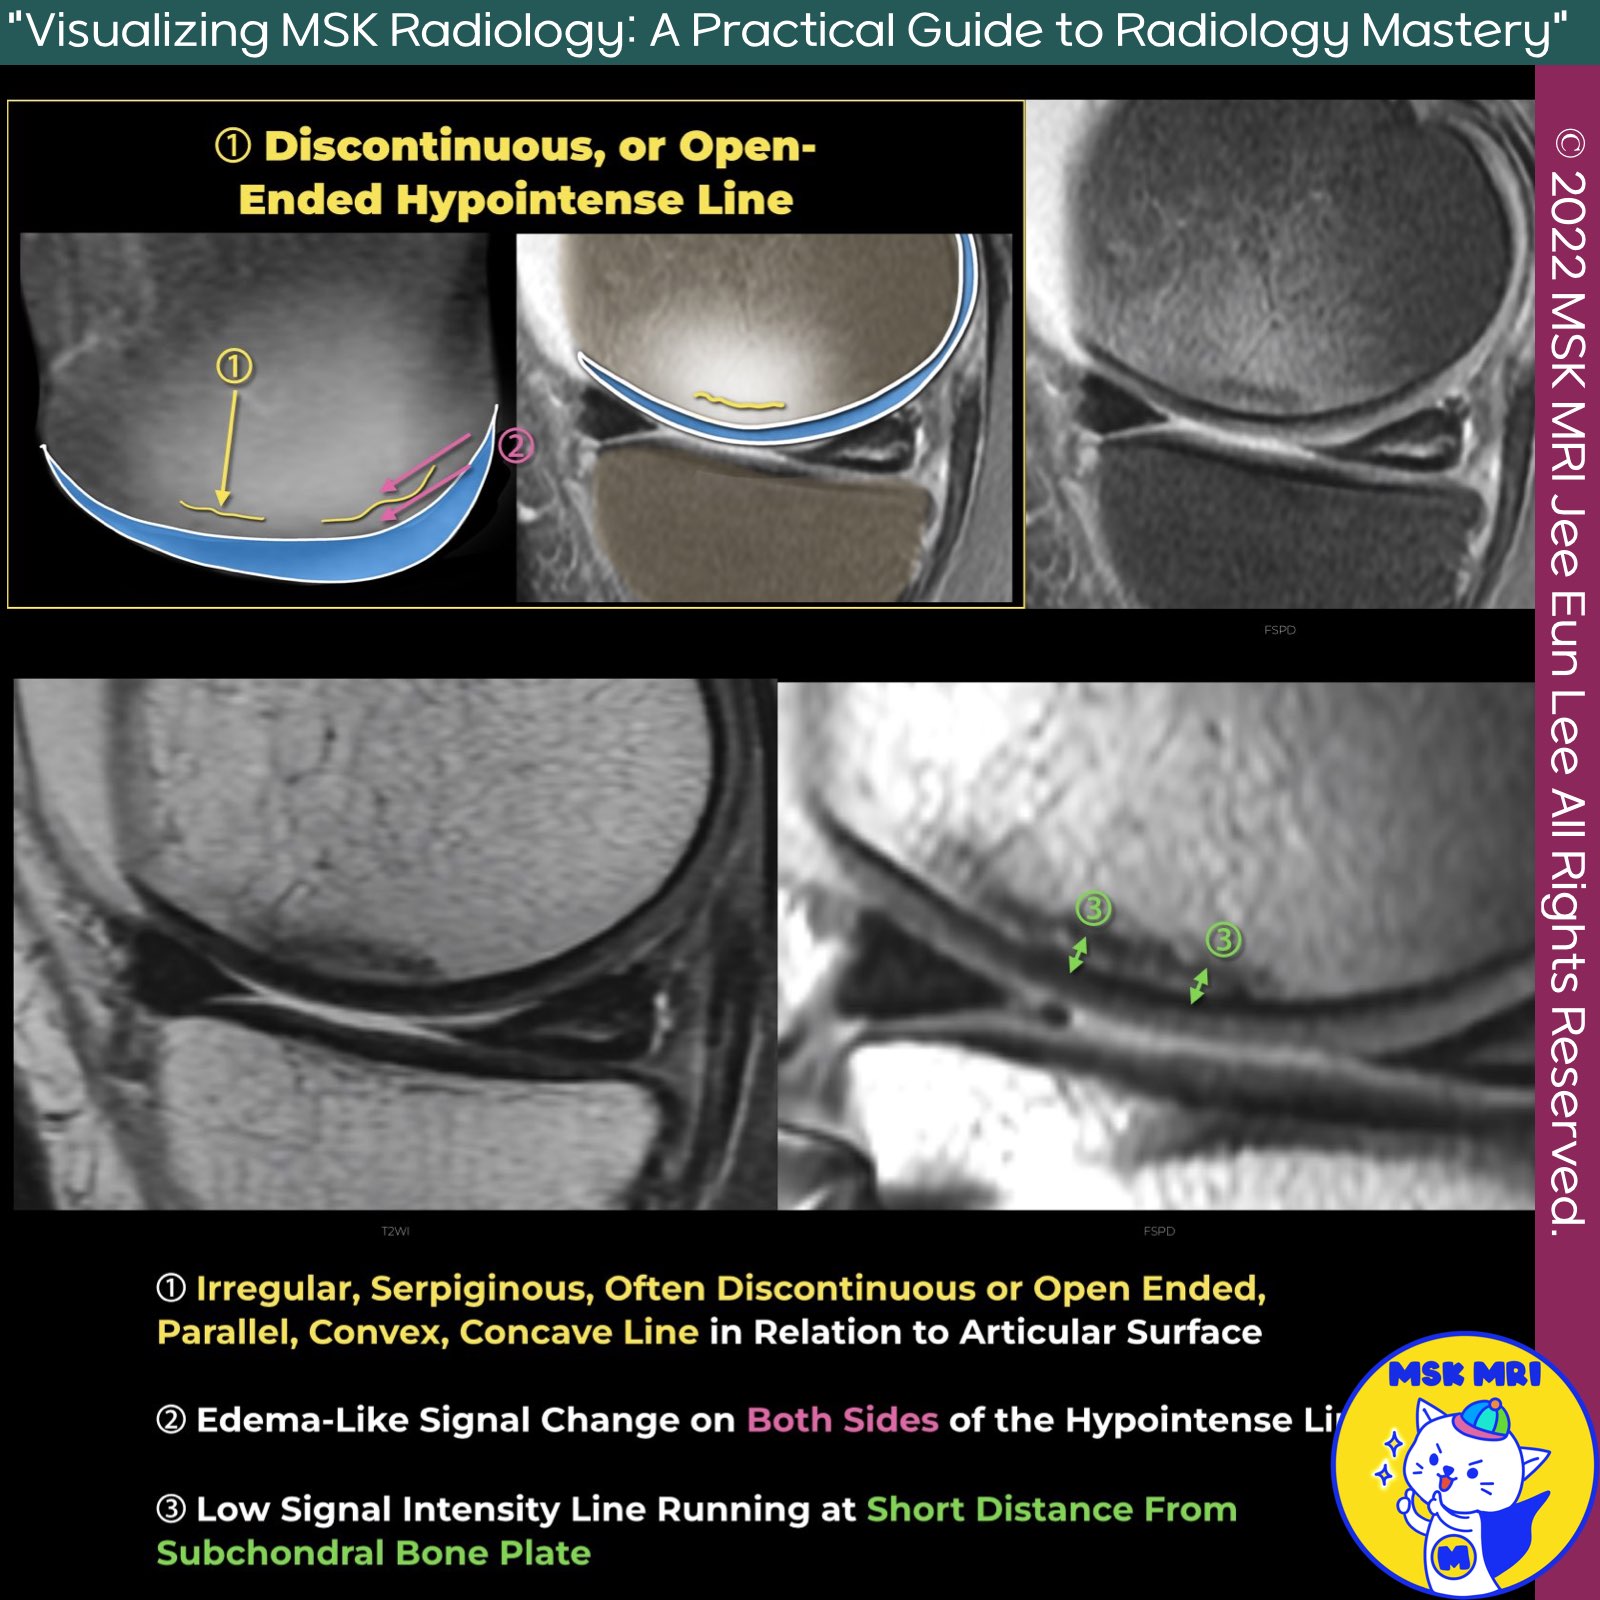

✅ No Epiphyseal Collapse with Hypointense Fracture Line

- This session focuses on cases without epiphyseal collapse but showing a discontinuous or open-ended hypointense fracture line.

The imaging findings can be summarized into three main characteristics:

1. Irregular, Serpiginous Line: An irregular, serpiginous, often discontinuous or open-ended line that is parallel, convex, or concave to the articular surface.

2. Edema-like Signal Change: Edema-like signal change on both sides of the hypointense line.

3. Low Signal Intensity Line: A low signal intensity line running short distances from the subchondral bone plate.